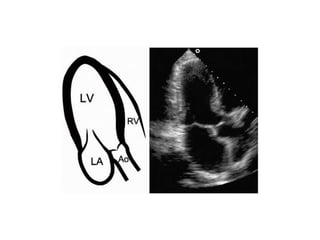

PLAX

MEDIAL ANGULATION - RIGHT VENT INFLOW